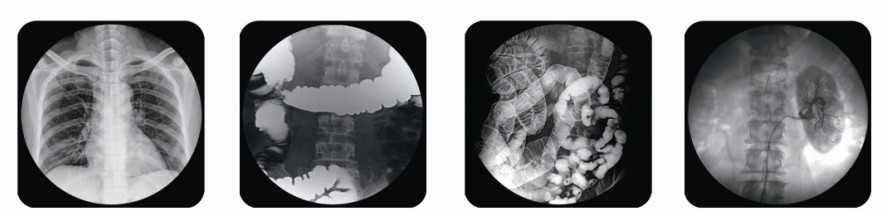

腸胃造影x光機其實也就是胃腸機,雖然該設備叫腸胃造影x光機但它功能還有很多,比如:可用于消化道造影、膽道造影、泌尿道造影以及下肢靜脈造影檢查患者身體各部位攝影、透視及其它創(chuàng)傷性常規(guī)檢查,可透視下進行骨折整復、取異物等工作。功能很全面,是醫(yī)療單位的首選設備。

目前,普朗公司推出的腸胃造影x光機9款可供用戶們選擇,下面為您展示的其中一款,點擊圖片下方紅色產品名稱可查看該產品的詳細介紹,另外您還可以通過電話聯(lián)系我公司客服了解普朗酶標儀、洗板機、病人監(jiān)護儀、c型臂、小兒呼吸機等產品信息。

(普朗醫(yī)療——高頻醫(yī)用診斷X射線機PLD5800腸胃造影x光機))